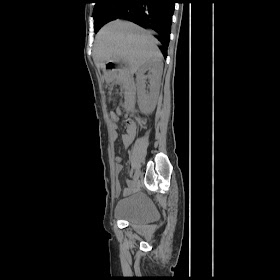

Radiological images:

CT-Scan investigation done on 16Apr16